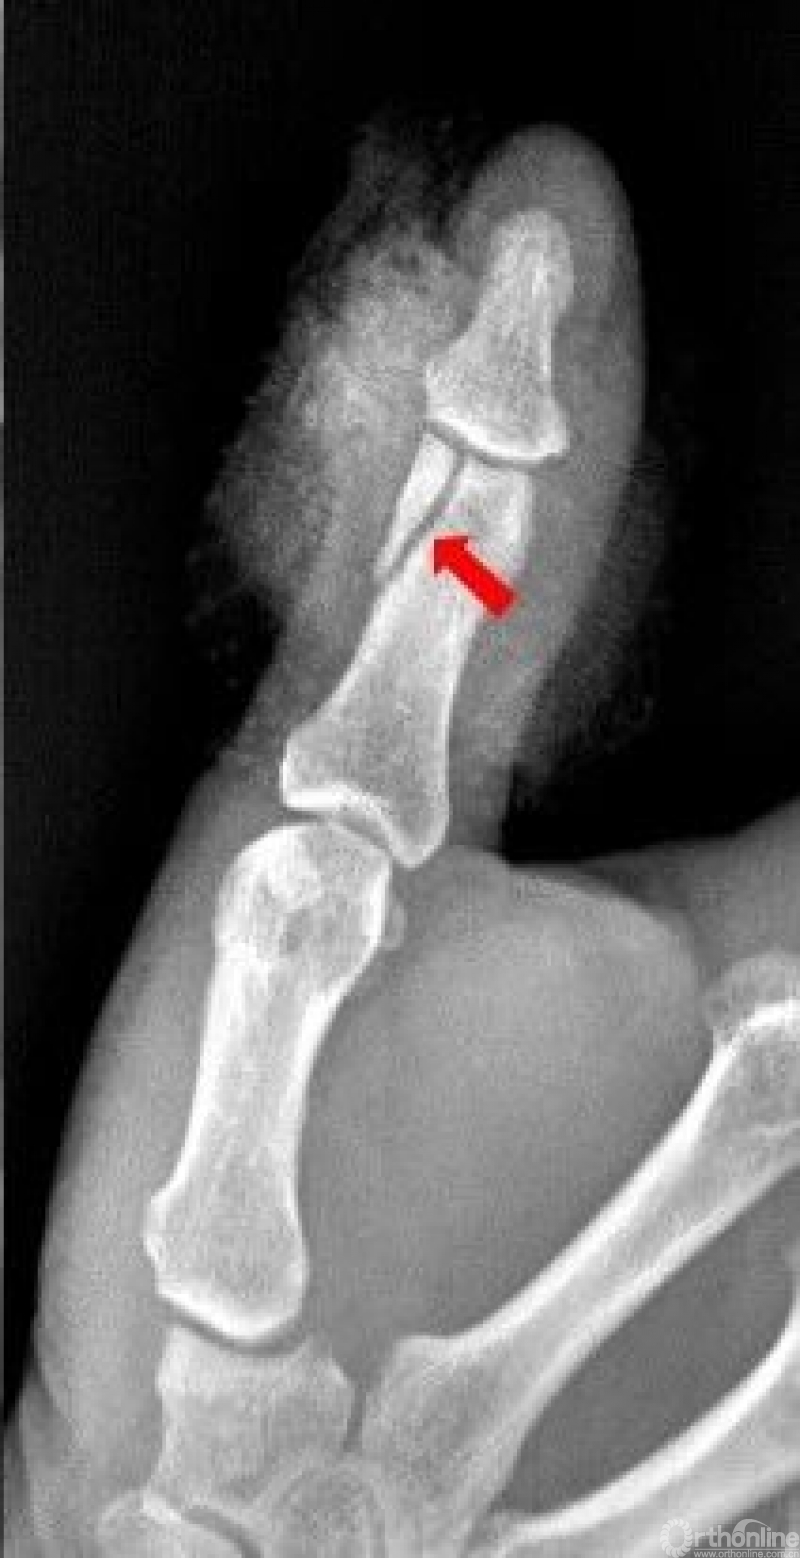

右手中指远节近端背侧关节处见游离骨片影。右手中指远节骨折